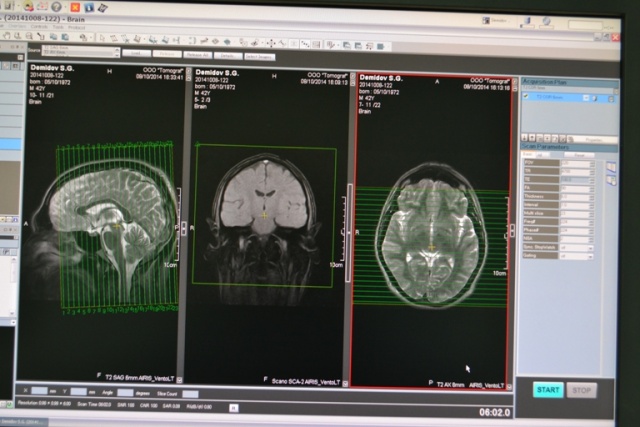

Как проводится МРТ?

Перед исследованием удаляются все металлические предметы на теле (на одежде и украшения). Исследование проводится в положении лежа на спине. Очень важно, чтобы пациент находился в расслабленном и неподвижном состоянии во время сканирования. Иногда перед проведением процедуры могут быть назначены седативные препараты для уменьшения тревоги и достаточного расслабления пациента. Взаимодействие с рентгенолаборантом сохраняется в течение всей процедуры. Во время сканирования возникают повторяющиеся, щелкающие звуки. Время проведения процедуры зависит от исследуемой области тела, это может занимать от 15 минут до полутора часов.

Используется томограф открытого типа, пациент находится в более комфортных условиях, чем в томографах закрытого типа. Людям, склонным к клаустрофобии, показано проходить диагностику на томографе именно открытого типа, на котором работают специалисты в «Томографе». Отметим, что в томографах закрытого типа во время МРТ-сканирования пациент находится в замкнутом пространстве внутри магнитной трубы. Некоторые пациенты могут испытывать ощущение клаустрофобии во время исследования.